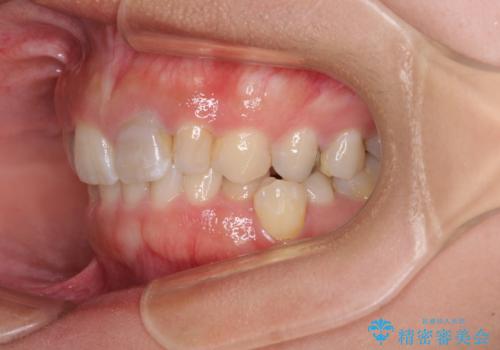

歯列から飛び出た歯 ワイヤー矯正で整った歯列に

- 下顎の歯列から飛び出した小臼歯を気にして来院された患者様です。

歯列以外に、上顎左右側切歯が矮小歯であり、上顎4前歯は失活していたため、矯正治療で歯列を整えるとともに上顎前歯の幅を調整し、矯正治療後にオールセラミッククラウンにて審美歯科治療を行うこととしました。

下顎の小臼歯を移動しきるのに2年弱の期間を要することとなり、補綴治療も合わせて2年半ほどの治療期間となりました。

口元の印象が大きく改善し、患者様には大変満足していただけました。